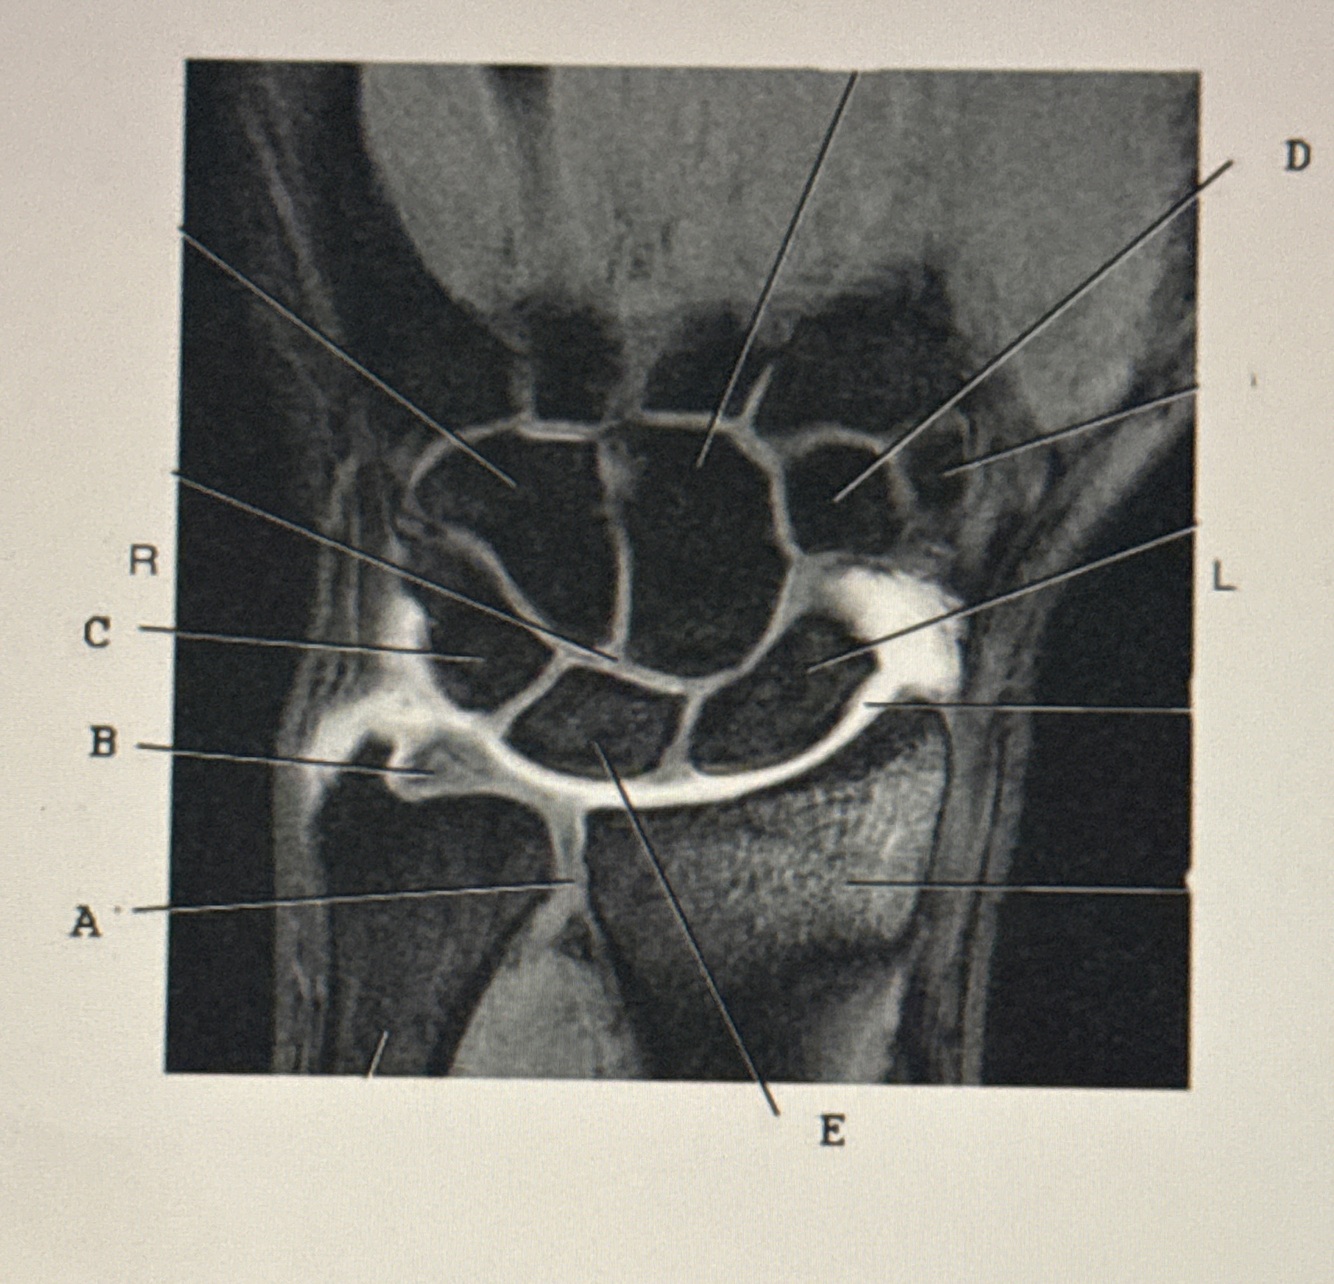

Q

C?

A

Triquetrum